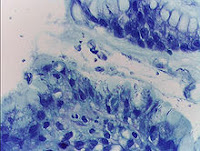

Gastrit, mide mukozasının iltihaplanmasıdır.

Gelişmiş toplumlarda insanların %10’unda, gelişmemiş toplumlarda ise %80’inde bulunan Helicobacter pylori de insanlarda midenin iç yüzeyinde kronik inflamasyon yaratarak gastrite neden olan bir bakteridir. Helicobacter pylori bakterisi yok edilmeden tedaviden sonuç almak mümkün değildir.